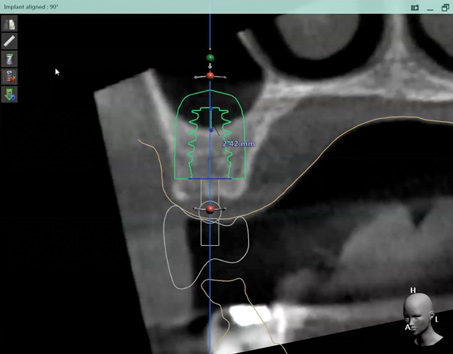

Fig 12. Virtual planning of a posterior implant (Fig 12) resulted in inadequate restorative running room for the crown emergence profile in the cross-sectional CBCT image. Revision (Fig 13) resulted in deeper positioning of the implant for restorative running room but necessitated transcrestal sinus elevation, possibly with the addition of bone via the osteotomy to tent the membrane.

Figure 12

Fig 13. Virtual planning of a posterior implant (Fig 12) resulted in inadequate restorative running room for the crown emergence profile in the cross-sectional CBCT image. Revision (Fig 13) resulted in deeper positioning of the implant for restorative running room but necessitated transcrestal sinus elevation, possibly with the addition of bone via the osteotomy to tent the membrane.

Figure 13